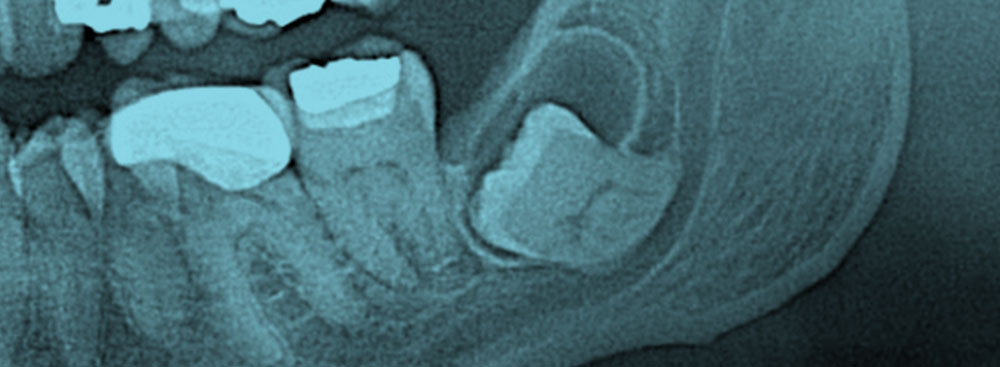

Quistes y tumores de los maxilares

Los quistes y tumores representan una de las principales causas de destrucción de los maxilares. En general se originan a partir de restos celulares de los tejidos que forman los dientes y suelen ser asintomáticos en etapas iniciales. El tratamiento de la mayoría de estas lesiones es la cirugía. En este contexto, la consulta a tiempo es esencial para minimizar el daño.